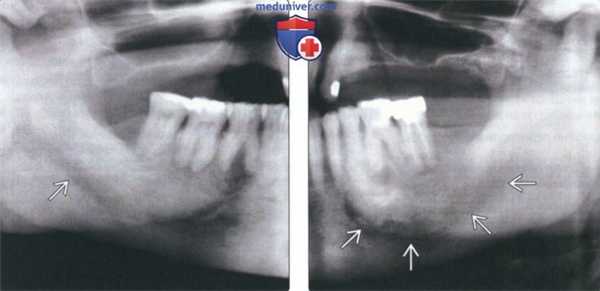

(Слева) На панорамной рентгенограмме определяется склеротическая фаза БП нижней челюсти справа. Трабекулы утолщены и склерозированы, нижняя кортикальная пластинка неразличима. Нижнечелюстной канал отчетливо визуализируется на фоне остеосклероза.

(Справа) На панорамной рентгенограмме у этого же пациента определяется поражение нижней челюсти слева. Хорошо отграниченное просветление в области премоляров-моляров - проявление более ранней стадии заболевания.